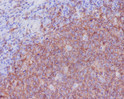

| Short Description | Rabbit monoclonal anti-CD20 for use in WB, IHC-P and FC in Human samples. Datasheet included with dilution recommendations, and related reagents. |

| Applications | WB/IHC-P/FC |

| Dilution Range | WB 1:500-1:1000IHC 1:50-1:100FC 1:50-1:100 |